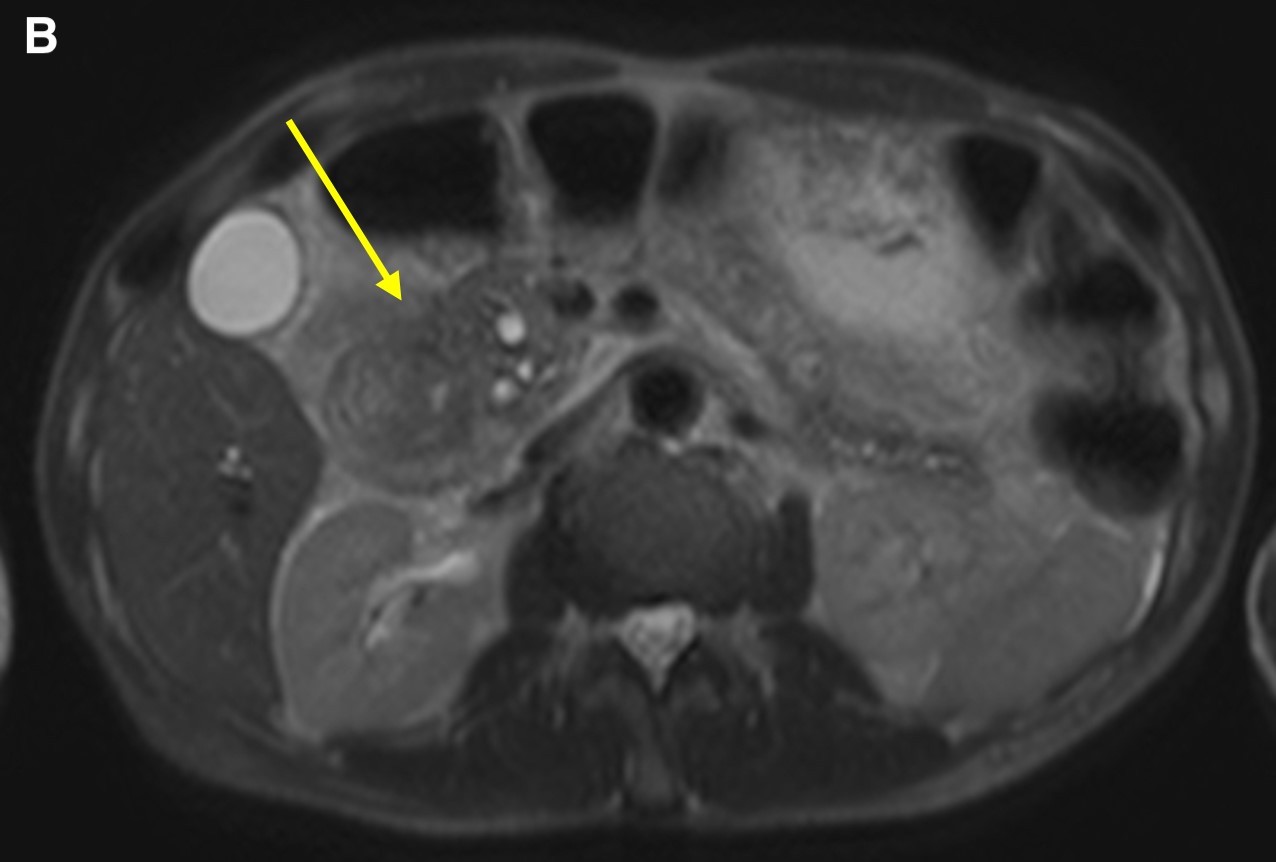

On magnetic resonance imaging (MRI) scans, groove pancreatitis often shows a T1 hypointense “sheet like” mass in the groove space.6 Depending on timing, T2 can demonstrate hypointensity, isointensity, or hyperintensity in this region.1 The initial phase of disease shows T2 hyperintensity, with progression into isointensity or hypointensity caused by fibrosis as the disease course continues.1 Cysts or cystic masses can be seen in the duodenal wall or groove space in T2-weighted imaging, as we saw in our patient (Figure 3).1 Magnetic resonance cholangiopancreatography can be helpful, as it can also demonstrate nonspecific signs such as common bile duct/pancreatic duct dilation.1 Gadolinium-enhanced images show delayed enhancement caused by fibrosis, as we saw in our patient (Figure 4). In one study, approximately 93% of patients showed patchy, late, post-gadolinium enhancement of the pancreas.7 In both the pure and segmental forms of groove pancreatitis, authors of one study found medial wall of the duodenum involvement with mural cysts on T2 weighted imaging.8 In cases of segmental groove pancreatitis, the common bile duct shows gradual tapering, while in cases of malignancy, the duct shows abrupt cutoff, which we saw in our patient (Figure 5).6

Figure 3. Axial T2-weighted scans demonstrated a cystic lesion in the thickened duodenal wall (a, arrow). Soft tissue thickening is seen in the groove between the pancreatic head and the second portion of the duodenum (b, arrow). Duodenal wall thickening (c, small arrow) and hypointensity (c, long arrow) was seen in the pancreatic head.